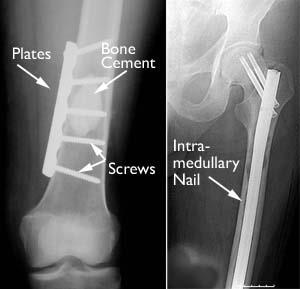

Prostate Cancer Metastasis Xray - Prostate Carcinoma Presenting With Diffuse Osteolytic Metastases And Supraclavicular Lymphadenopathy Mimicking Multiple Myeloma Idowu 2018 Clinical Case Reports Wiley Online Library : The earlier the detection of prostate cancer, the better the patient's chance of survival is.. However, as with other types of cancer,. If you have been diagnosed with adenocarcinoma cancer, you have a cancer that developed in one of the glands that lines the inside of your organs. The earlier the detection of prostate cancer, the better the patient's chance of survival is. Prostate cancer is one of the most common types of cancer diagnosed in men. But hearing the words can still be scary.

If you have been diagnosed with adenocarcinoma cancer, you have a cancer that developed in one of the glands that lines the inside of your organs prostate cancer xray. One in seven men in the united states will receive a prostate cancer diagnosis during his lifetime.